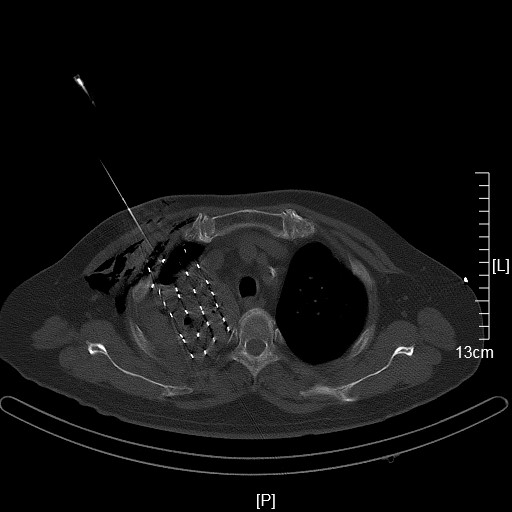

运城同德医院成功为一名肺癌患者行经皮穿刺125-碘粒子植入术